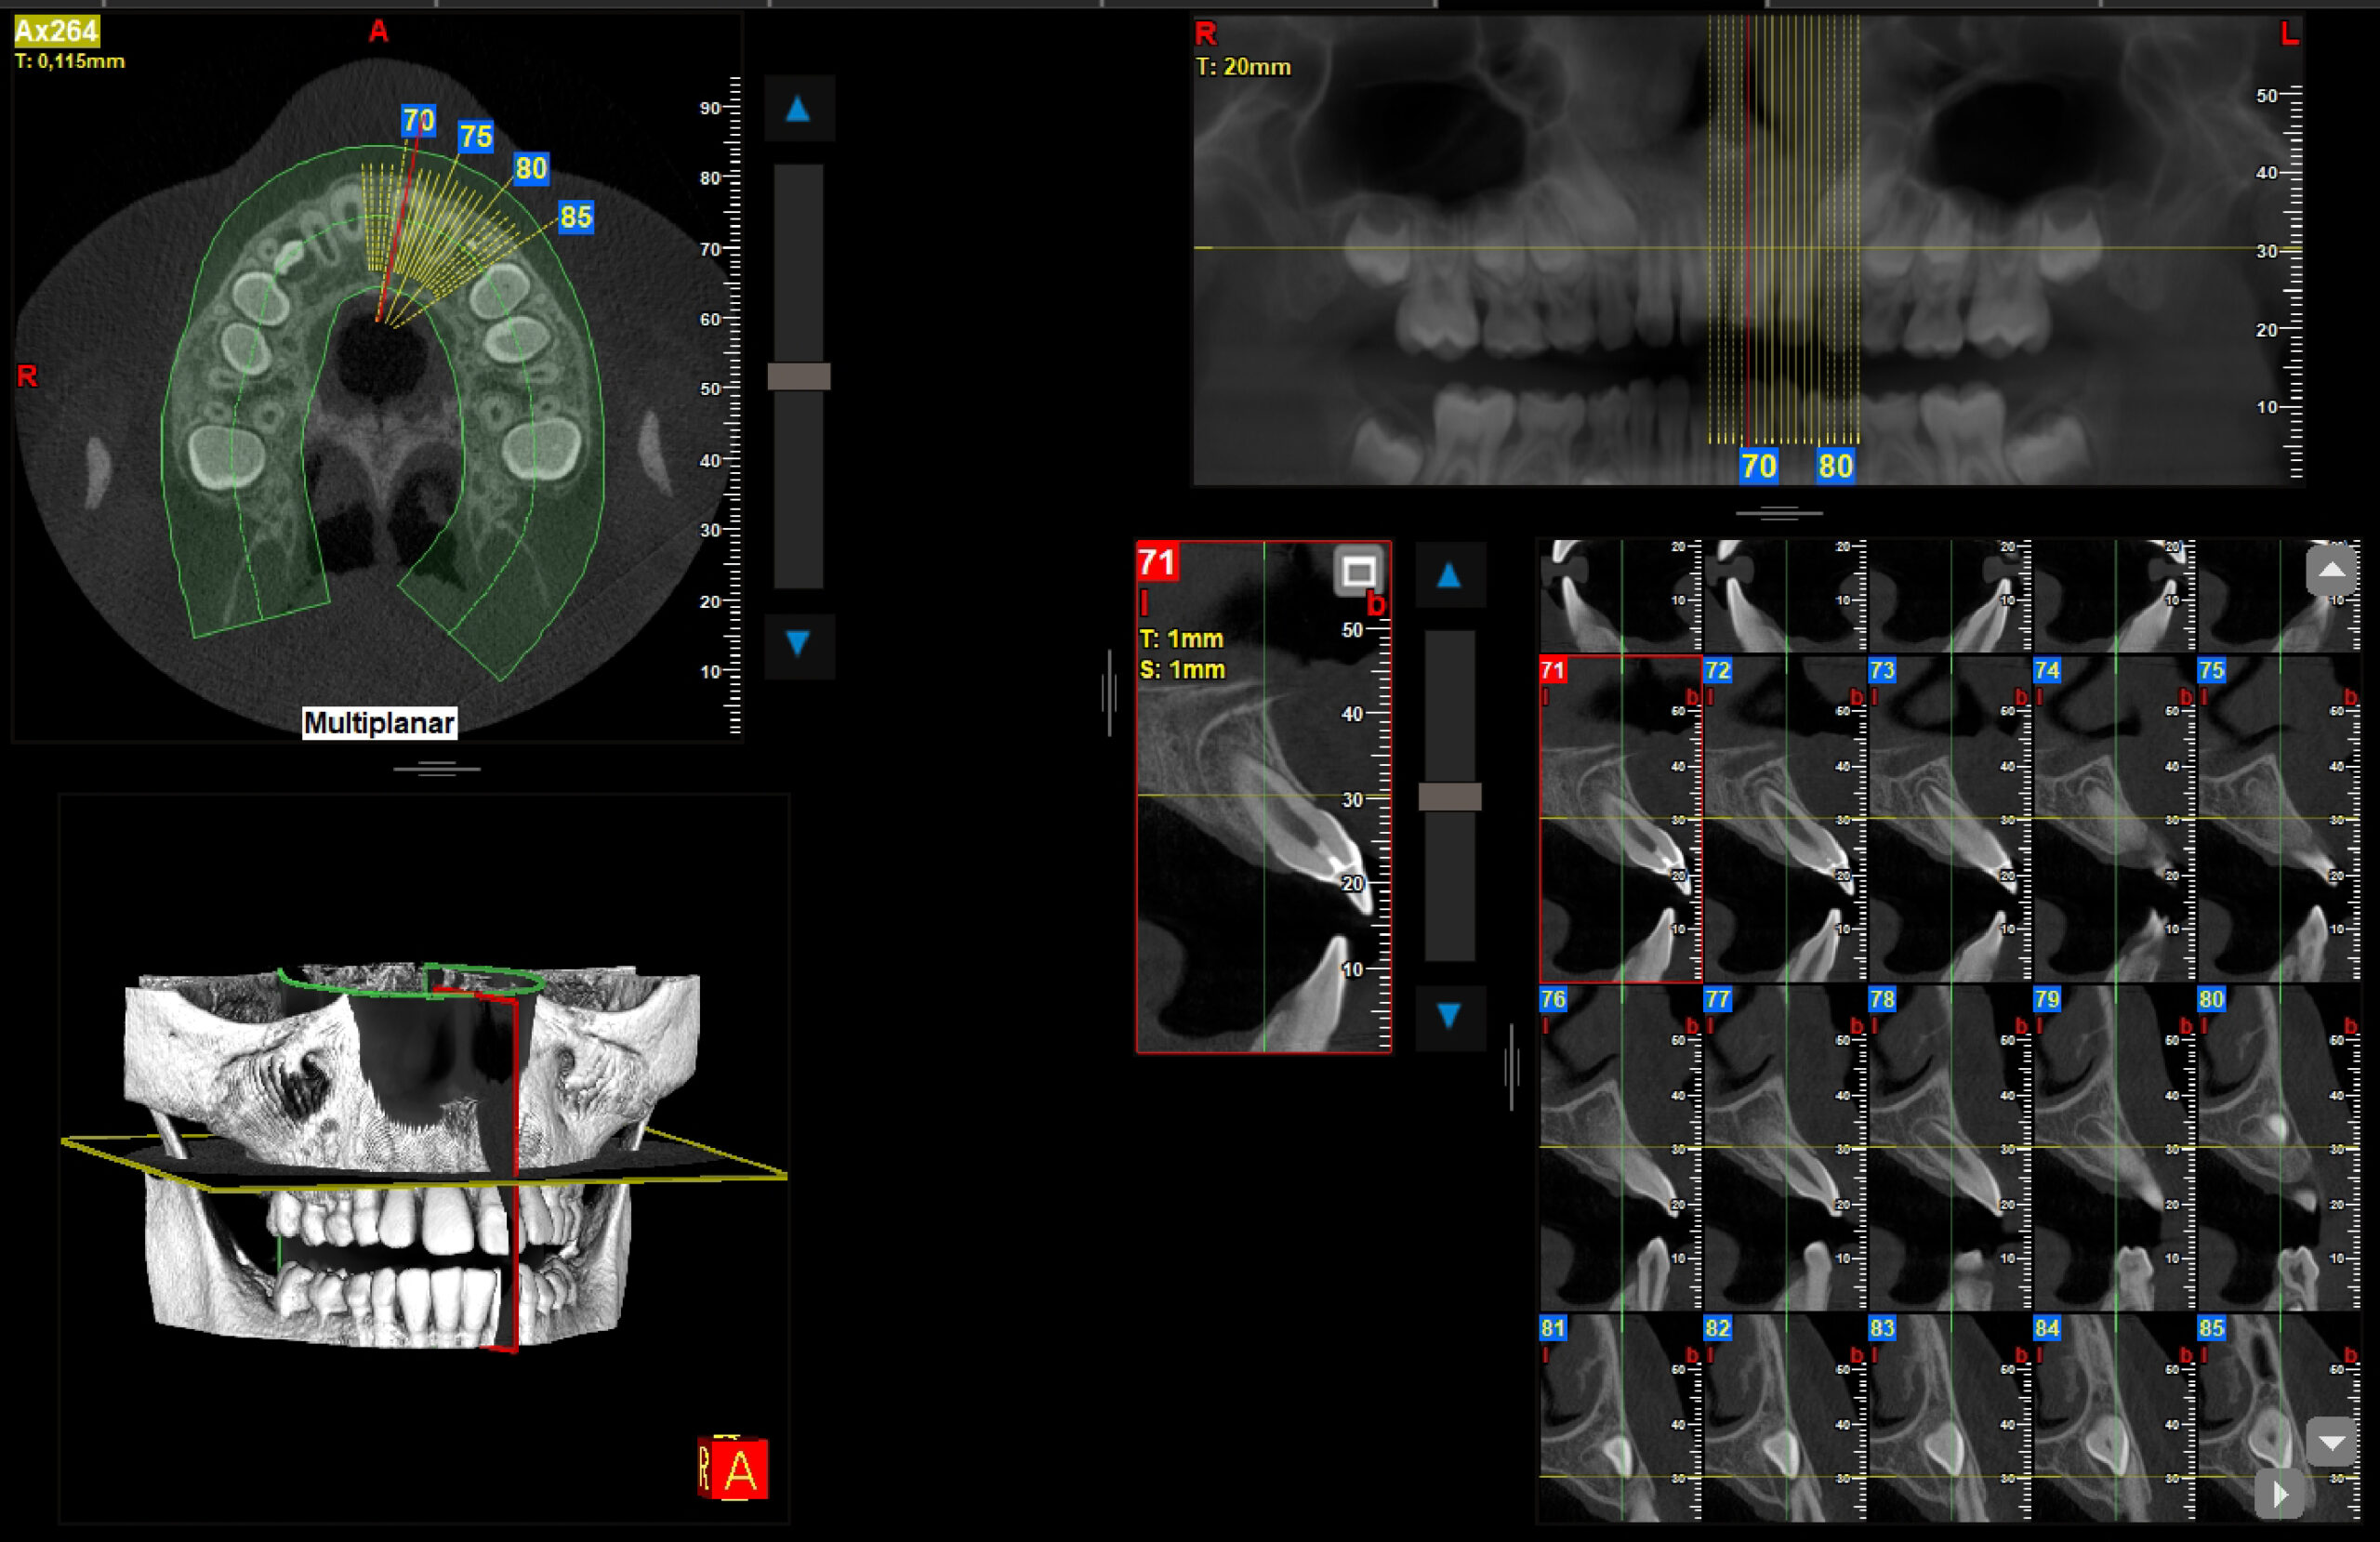

2.1 fractura coronal

Radiografías